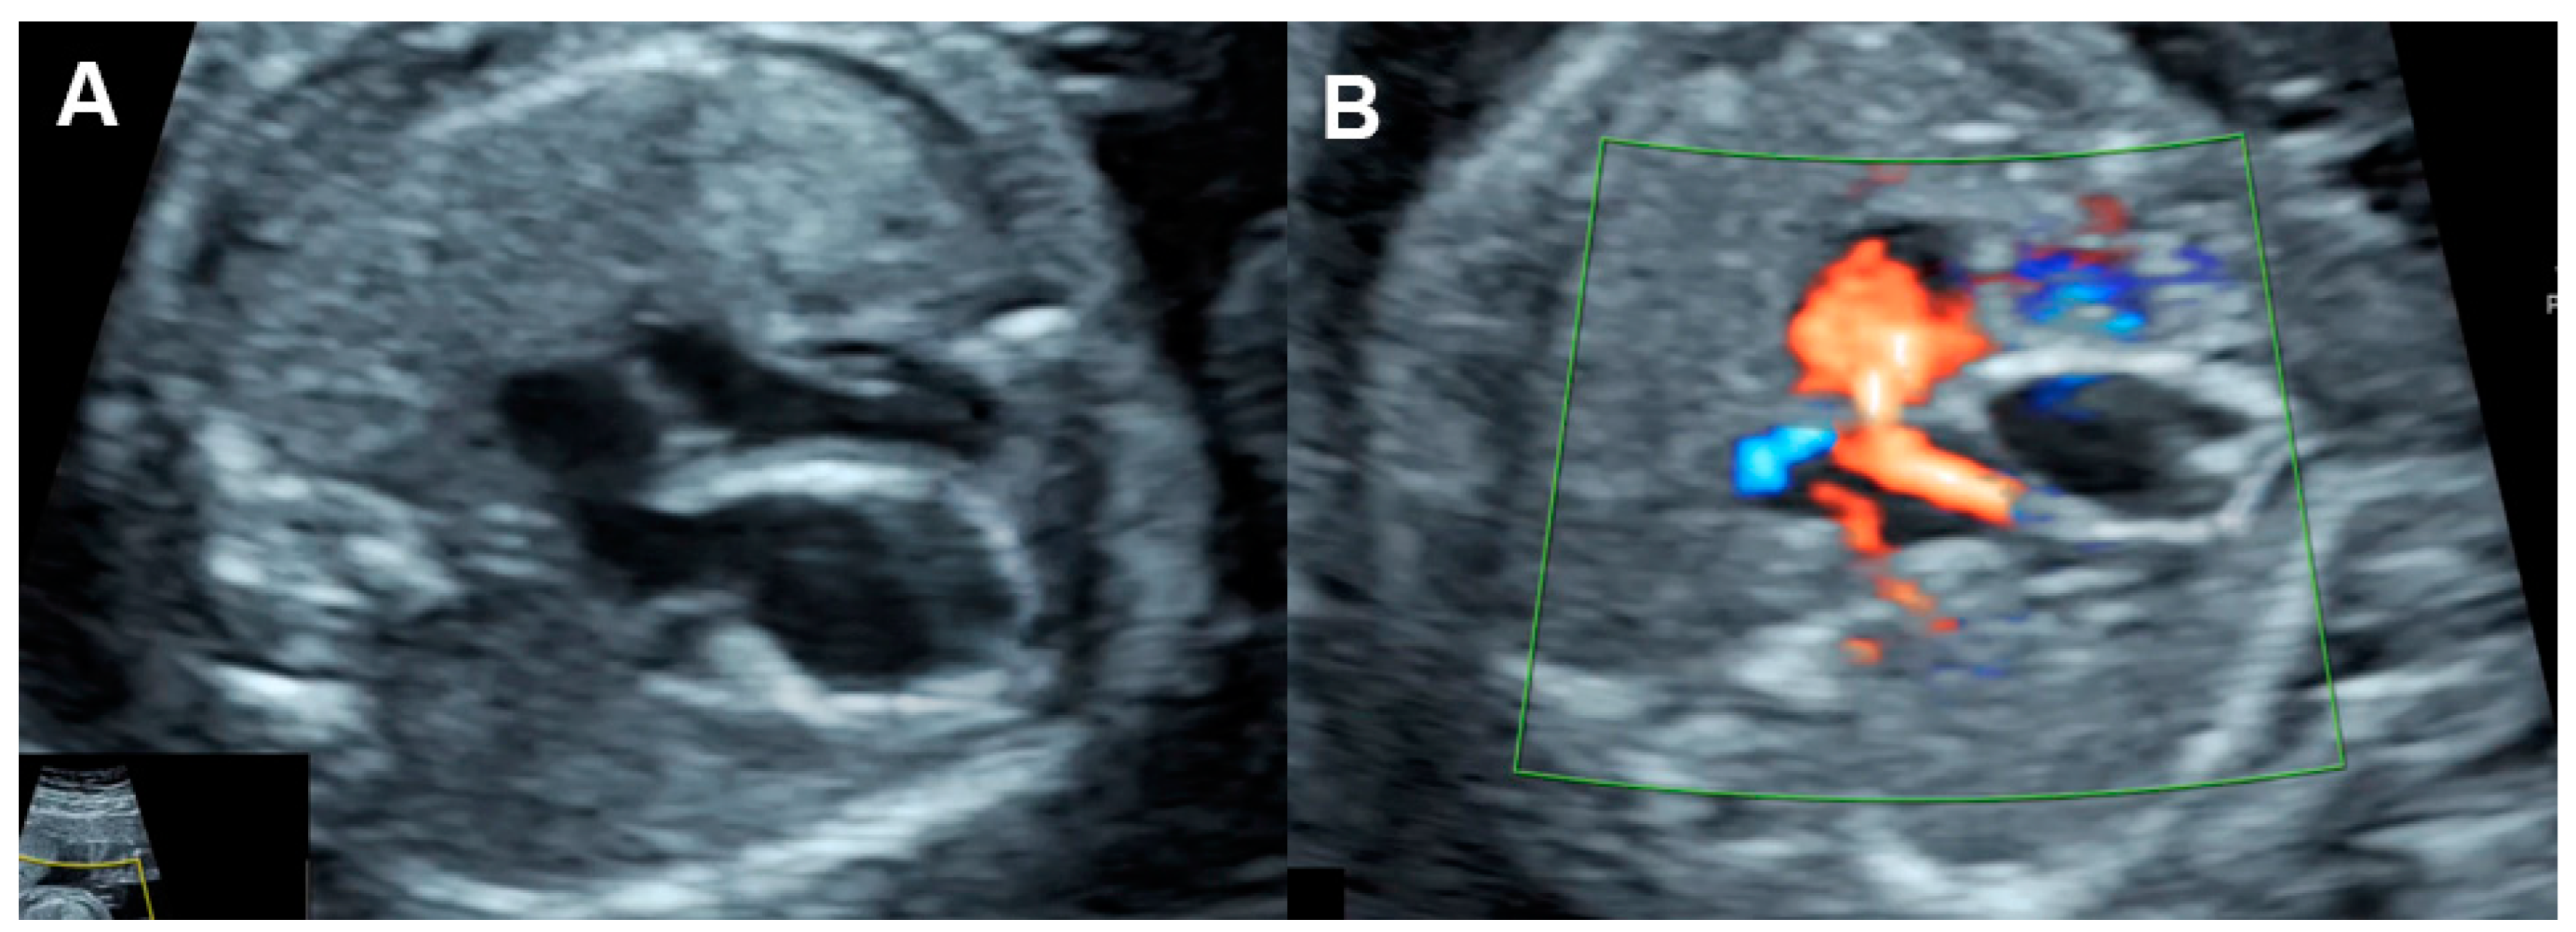

| Parameters | Abnormal Changes | Interpretation |

|---|---|---|

| Dimension | ||

| Cardiothoracic area ratio | Increased >35% | Cardiac enlargement |

| Cardiothoracic diameter ratio | Increased >95th centile | Cardiac enlargement |

| Inflow characteristics | ||

| Filling time fraction | Decreased | Diastolic dysfunction |

| E/A ratio | Monophasic | Diastolic dysfunction |

| Decreased | Diastolic dysfunction | |

| Increased | Volume loading/External compression | |

| Venous PW Doppler | ||

| Inferior vena cava | Reversed A-wave >20 cm/s | Diastolic dysfunction /increased venous pressure |

| Decreased S-wave | Tricuspid regurgitation | |

| Ductus venosus | Absent or reversed A-wave | Diastolic dysfunction/increased venous pressure |

| Performance | ||

| Shortening fraction | Decreased (<28%) | Systolic dysfunction |

| Increased | Reduced afterload/increased contractility | |

| Ejection fraction | Decreased <50%) | Systolic dysfunction |

| Cardiac output (Stroke volume) | Decreased (Z < −2) | Systolic dysfunction/poor filling |

| Increased (Z > +2) | Reduced afterload/volume load | |

| Tei index | Increased > 0.50 | Global cardiac dysfunction |

| ICT: 28 (22–33) ms | Prolonged | Systolic dysfunction |

| IRT: 34 (26-41) ms | Prolonged | Diastolic dysfunction |

| Systolic strain/Strain rate | Increased | Reduced afterload |

| Decreased | Reduced contractility | |

| E/Vp (Color M-mode) | Increased | Diastolic dysfunction |